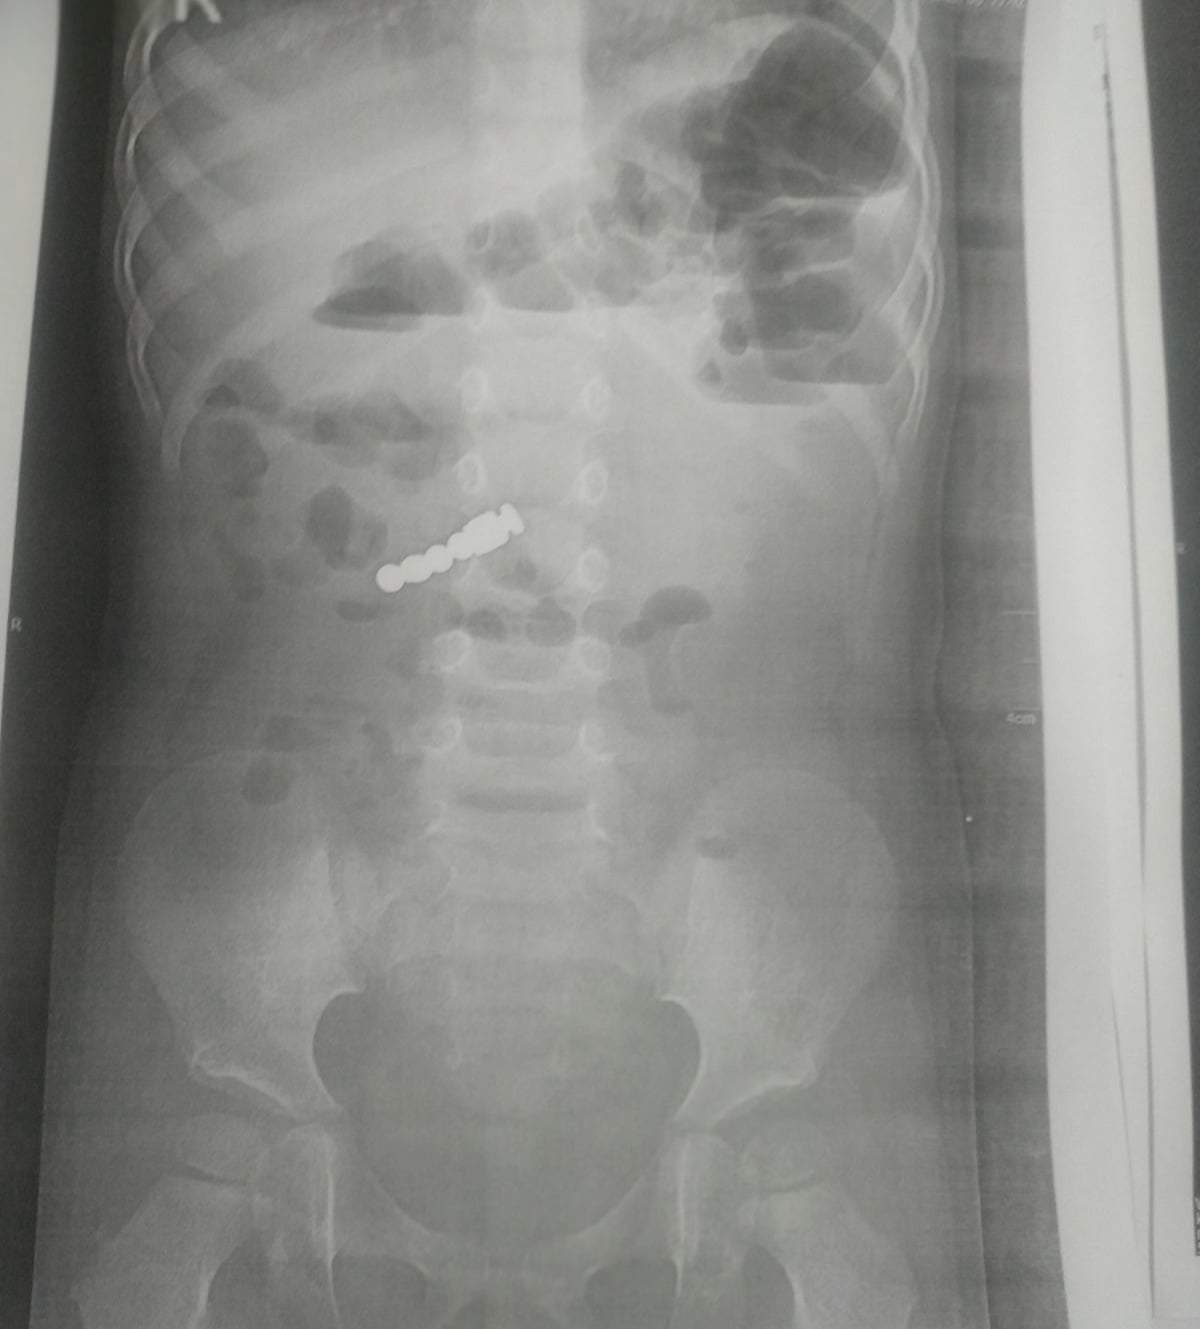

Ребенок проглотил магниты / Фото "Охматдета"

У девочки были только рвота и повышенная температура. Чтобы установить причину этих симптомов, врачи районной больницы сделали ребенку рентген. Они увидели на снимках 4 магнита.

"С ними малышку доставила скорая в "Охматдет". Доставали их наши хирурги с помощью современного электронно-оптического преобразователя (ЭОП) в ургентной операционной, что обеспечило точные и успешные манипуляции разного уровня сложности", – рассказали в больнице.